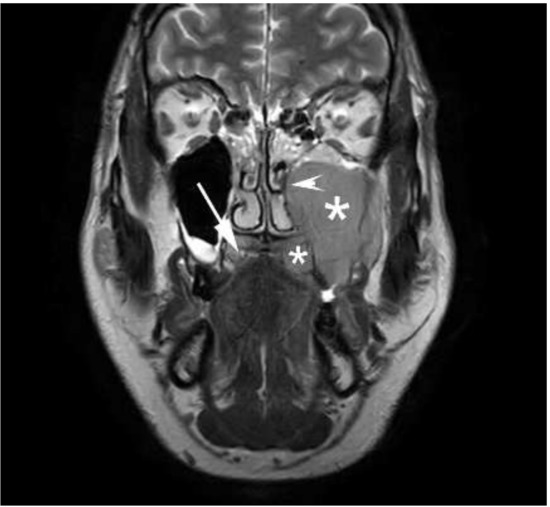

1.1. Case Report